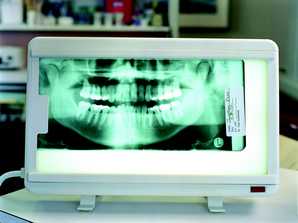

However, the human eye is only capable of distinguishing 32 shades of gray, which corresponds to a spatial frequency ranging from 5 to 7 lp/mm without magnification. The question then becomes, does the magnitude of a digital system spatial resolution above about 10 lp/mm make any diagnostic difference in the clinician’s ability to recognize pathosis radiographically? The answer is still being debated, but at least from our viewpoint, which can be supported from some of our initial investigations into this question, 1,2 probably not. Therefore as an example, can dentists recognize carious lesions confined to enamel as well using digital images as compared to radiographic film? Probably so, but further investigation is needed. An example of an image taken with a Soredex OpTime (spatial resolution of 12.5 lp/mm) is shown in Figure 1. An arrow is pointing to noncavitated proximal carious lesions.

Finally, overall appearance of the image can be a very subjective assessment. Most dentists prefer image appearance and definition to be as much like conventional film as possible. The bitewing image in Figure 2 was taken with a CCD sensor and the bitewing image in Figure 3 was taken with a Soredex OpTime PSP sensor using a dry skull to maximize the definition of bone. Both images were made using the same kV, mA, and time, using the same enhancement features of the particular post-processing software utilized by the imaging system. From a purely subjective viewpoint, some dentists may prefer one image over the other depending on their personal likes and dislikes.